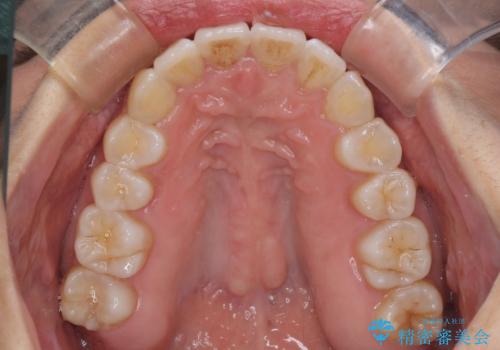

骨格的な問題を抱えた左奥以外は比較的早く咬み合わせが改善しましたが、左奥はどこで咬み合えば良いのか分からず、大変不便な思いをされていました。

ゴムかけにご協力いただき、最終的には反対咬合を改善することができ、患者様には大変満足していただきました。

歯列全体の拡大と、歯と歯の間を削ることでスペースを獲得し、インビザラインによる矯正治療を行うこととしました。